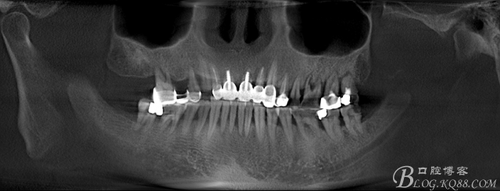

1、牙周炎是可以种牙的。种牙和是否有牙周炎是没有多大关系的,但是如果要想种牙的效果好的话,最好是先把牙周炎给治疗好,不然牙周炎本身就容易让牙齿松动,如果没有治好就种牙,通常效果不是很理想的。

如果发现牙周炎的话,最好及早去医院治疗,不然拖越久的话,可能炎症会更加严重,也会影响日常生活。想种牙的话,最好也是等治疗好牙周炎再去,这样才能达到最佳的效果,种牙也才有价值。同时,还有注意自己的饮食习惯,少吃对牙齿有刺激性的食物。